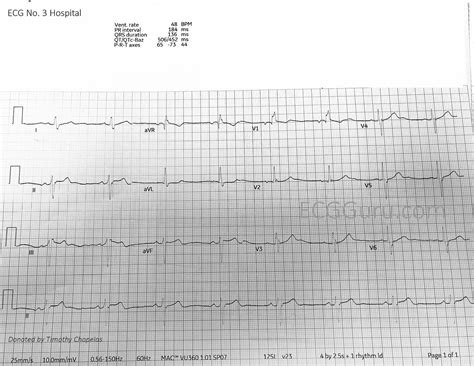

Inferior Mi ECG, short for Inferior Myocardial Infarction Electrocardiogram, is a specialized form of ECG that focuses on detecting myocardial infarctions (heart attacks) in the inferior wall of the heart. The inferior wall is the lower part of the heart, and infarctions in this region can be particularly challenging to diagnose due to their subtle symptoms and ECG changes.

Inferior Mi ECG involves placing electrodes in specific positions to capture the electrical activity of the heart from different angles. This allows cardiologists to identify patterns indicative of an inferior myocardial infarction. The standard 12-lead ECG is often used for this purpose, but additional leads may be employed to enhance diagnostic accuracy.

Interpreting Inferior Mi ECG results requires a thorough understanding of the ECG patterns associated with inferior myocardial infarctions. Key features to look for include:

• ST-Segment Elevation: Elevation of the ST segment in leads II, III, and aVF is a classic sign of an inferior myocardial infarction. This pattern indicates acute injury to the inferior wall of the heart.

• Q Waves: The presence of Q waves in leads II, III, and aVF suggests a previous myocardial infarction in the inferior wall. Q waves are pathological if they are wider than 0.04 seconds or deeper than 25% of the subsequent R wave.

• T-Wave Inversions: Inversions of the T waves in leads II, III, and aVF can also indicate an inferior myocardial infarction, particularly in the subacute phase.

It is important to note that the interpretation of Inferior Mi ECG results should be done by a qualified healthcare professional. Misinterpretation can lead to delayed or inappropriate treatment, potentially compromising patient outcomes.